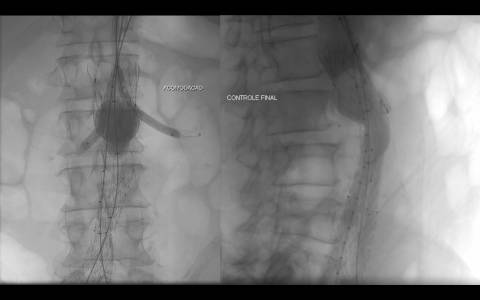

A avaliação por tomografia computadorizada evidenciou um aneurisma infra-renal de colo hostil e acessos vasculares com muita ateromatose. Diante do contexto clínico e de imagem foi optado pelo tratamento endovascular com endoprótese de baixo perfil Incraft CORDIS e técnica de Snorkel Grafts com stents Palmaz CORDIS para as artérias renais.